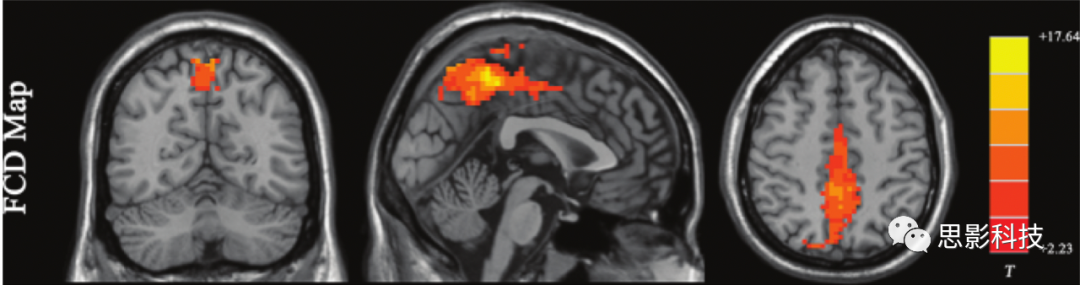

1)度功能連接度(FCD

FCD通過(guò)計(jì)算中某個(gè)體素與其他體素之間的BOLD時(shí)間序列的相關(guān)性,顯示該體素的功能連接強(qiáng)度(即高速路的“樞紐”),而非具體的連接路徑。還可以75mm為界,計(jì)算短距離和長(zhǎng)距離FCD。短程FCD是通過(guò)對(duì)每個(gè)體素和其周圍75 mm范圍內(nèi)的體素之間的時(shí)間序列進(jìn)行相關(guān)分析來(lái)測(cè)量的。短程FCD可以反映該體素周圍的區(qū)域Bold功能連接程度。長(zhǎng)程FCD是全腦FCD減去短程FCD的結(jié)果,可以反映長(zhǎng)距離功能連接程度。優(yōu)點(diǎn):基于體素的分析方法,分析方法簡(jiǎn)單,無(wú)需先驗(yàn)假設(shè);缺點(diǎn):不顯示連接路徑;可重復(fù)性一般。

200例健康志愿者FCD分析結(jié)果。